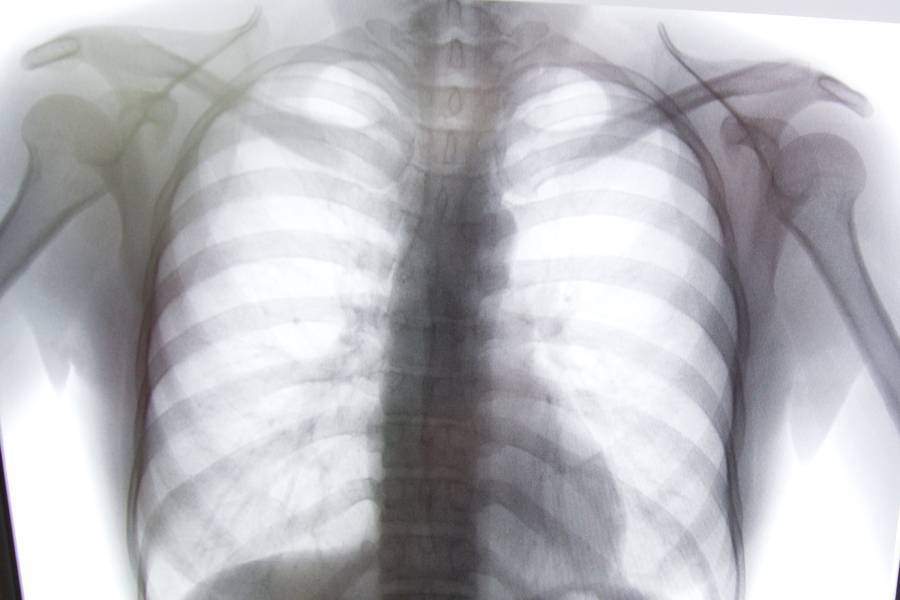

Рентгеновский снимок Фото: Андрей Гордеев / Ведомости/ТАСС